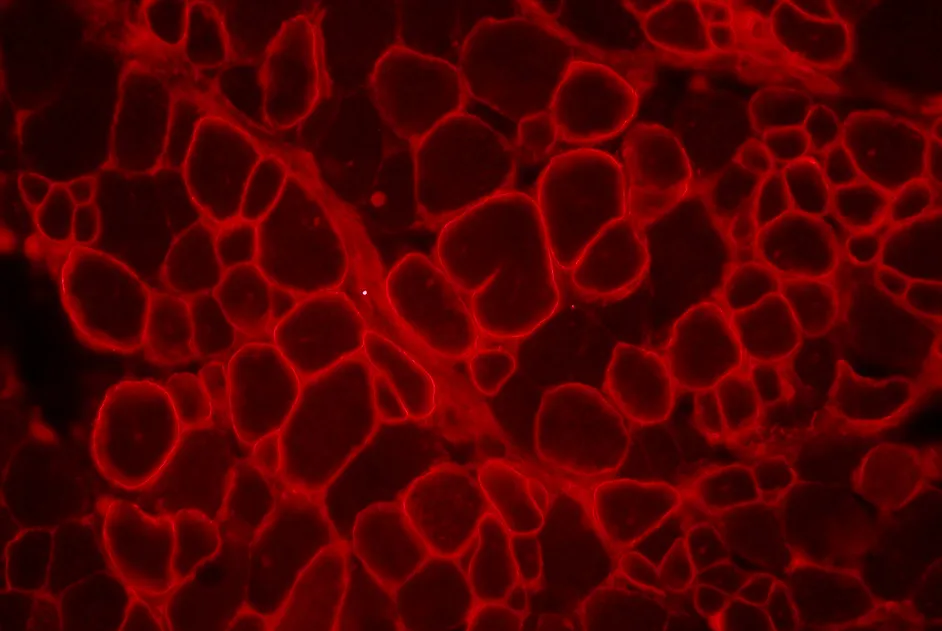

CMT associée à une atteinte rénale : le gène INF2 en cause

Mise en évidence de mutations dans le gène INF2 à l’origine de la maladie de Charcot-Marie-Tooth associée à une glomérulosclérose segmentaire et focale.